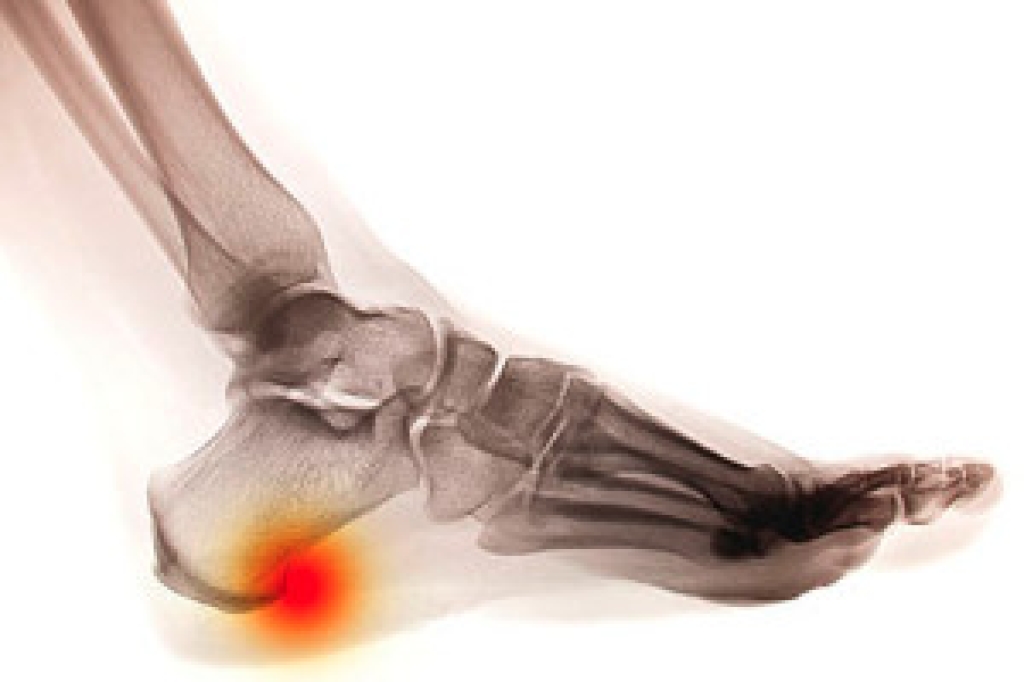

Systemic diseases affect the whole body, and symptoms usually are displayed in the feet. This condition can make a patient’s ability to walk unbearable. Systemic diseases include gout, diabetes mellitus, neurological disorders, and arthritis.

Gout – is caused by an excess of uric acid in the body. Common symptoms include pain, inflammation, and redness at the metatarsal/phalangeal joint of the base big toe. Gout can be treated by NSAIDs to relieve pain and inflammation, and other drugs that lower the acid levels in the body.